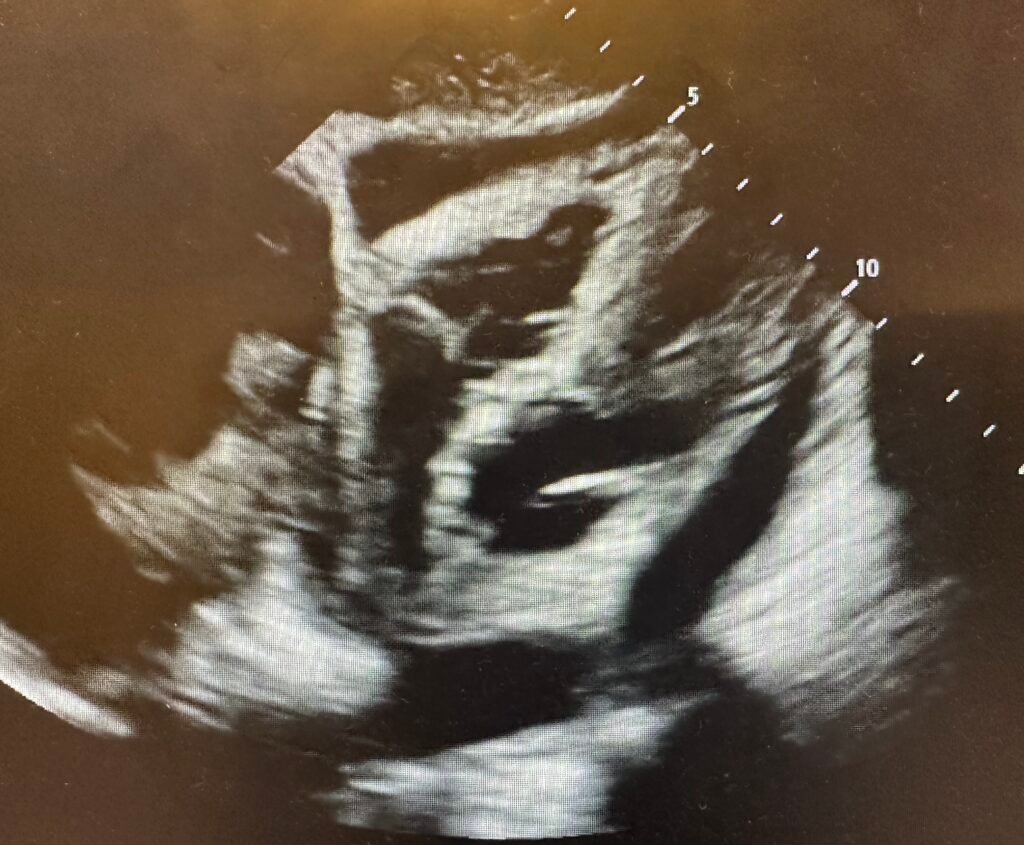

So a bedside echo was done:

Large effusion.

Diagnosis: Pericarditis.

- Dr. Smith’s approach quickly resolved this case. Starting from the likelihood of acute pericarditis (based on predisposing conditions — the absence of CP — and an ECG with a series of findings in favor of acute pericarditis) — quick performance of bedside Echo showing a large pericardial effusion was all that was needed to provide the needed confirmation.